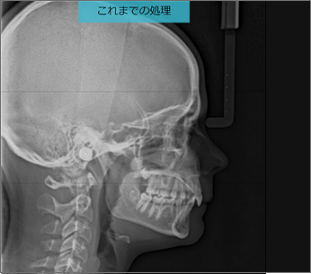

スキンラインの認識も骨の視認性も向上した新セファロ画像

- 新CS Adaptフィルターにより、スキンラインが認識しやすくなります。

- 画像強調をアップさせ、計測ポイントとなる骨の視認性も改善しています。

同一患者の治療中、別日程で撮影した画像